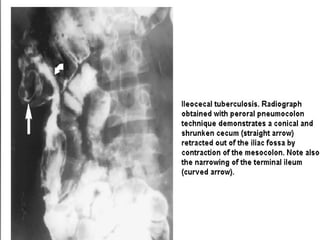

 Barium enemafor colon and ileocaecal region:  Thickened iliocaecal valve with a broad triangular appearance with the base towards the caecum (inverted umbrella sign or (Fleischner’s sign)  “Conical caecum”, shrunken in size and pulled out of the iliac fossa due to contraction and fibrosis of the mesocolon

 Loss ofnormal ileocaecal angle and dilated terminal ileum, appearing suspended from a retracted fibrosed caecum – goose neck deformity  Rapid transit and lack of barium retention indicating acute  inflammation - Sterlin’s sign  Narrow beam of barium due to stenosis - String’s sign

Loss of normal ileocaecalangle and dilated terminal ileum, appearing suspended from a retracted fibrosed caecum – goose neck deformity